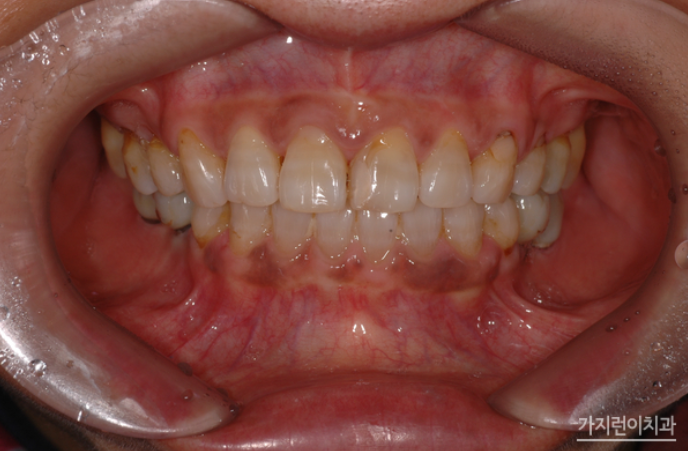

1년정도가 더 지나 모든 치료가 종결 되셨는데요. 교정과 임플란트를 병행했음에도 안정적인 구치부 교합이 만들어졌고, 상하악의 뻐드러짐도 말끔하게 개선되었습니다. 임플란트와 치아교정은 동시에 진행할 수 있을까? 라는 질문을 많이 받았는데요. 임플란트가 고정되어있기 때문에 교정이 조금만 틀어져도 틈이 벌어지는 등의 문제가 생겨날 수 있었습니다. 하지만 저희 서울가지런이치과 교정과 의원에서는 계획했던대로 치아의 이동이 잘 되었기 때문에 지정된 위치에 임플란트도 잘 식립했고 조화로운 교합상태가 되었습니다.

교정이 끝나고 3년이 지난 모습인데요. 나이가 들어 치아를 상실한 경우 보통은 임플란트만 하고 끝나겠지만 평소 뻐드러진 치아 콤플렉스를 개선하려는 환자의 의지와 바람이 의료진의 술기와 만나 좋은 시너지를 낼 수 있었던 케이스였습니다.